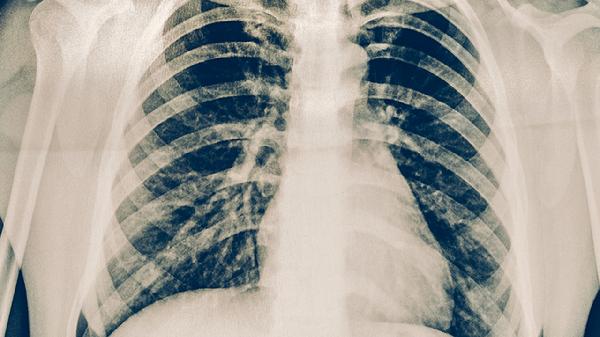

結(jié)核菌素試驗(yàn)陽性者需進(jìn)行胸部X線檢查,密切接觸者每半年復(fù)查1次。糖尿病患者、矽肺患者等高風(fēng)險人群應(yīng)每年做胸部CT篩查。出現(xiàn)咳嗽咳痰超過2周、低熱盜汗等癥狀時,需及時進(jìn)行痰涂片和GeneXpert檢測。